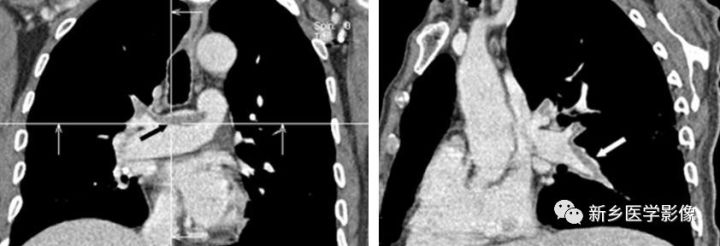

慢性肺动脉栓塞CT图像

a. 冠状位MPR  b. 矢状位MPR均显示偏心性肺动脉内充盈缺损(A图为黑箭、B图为白箭)